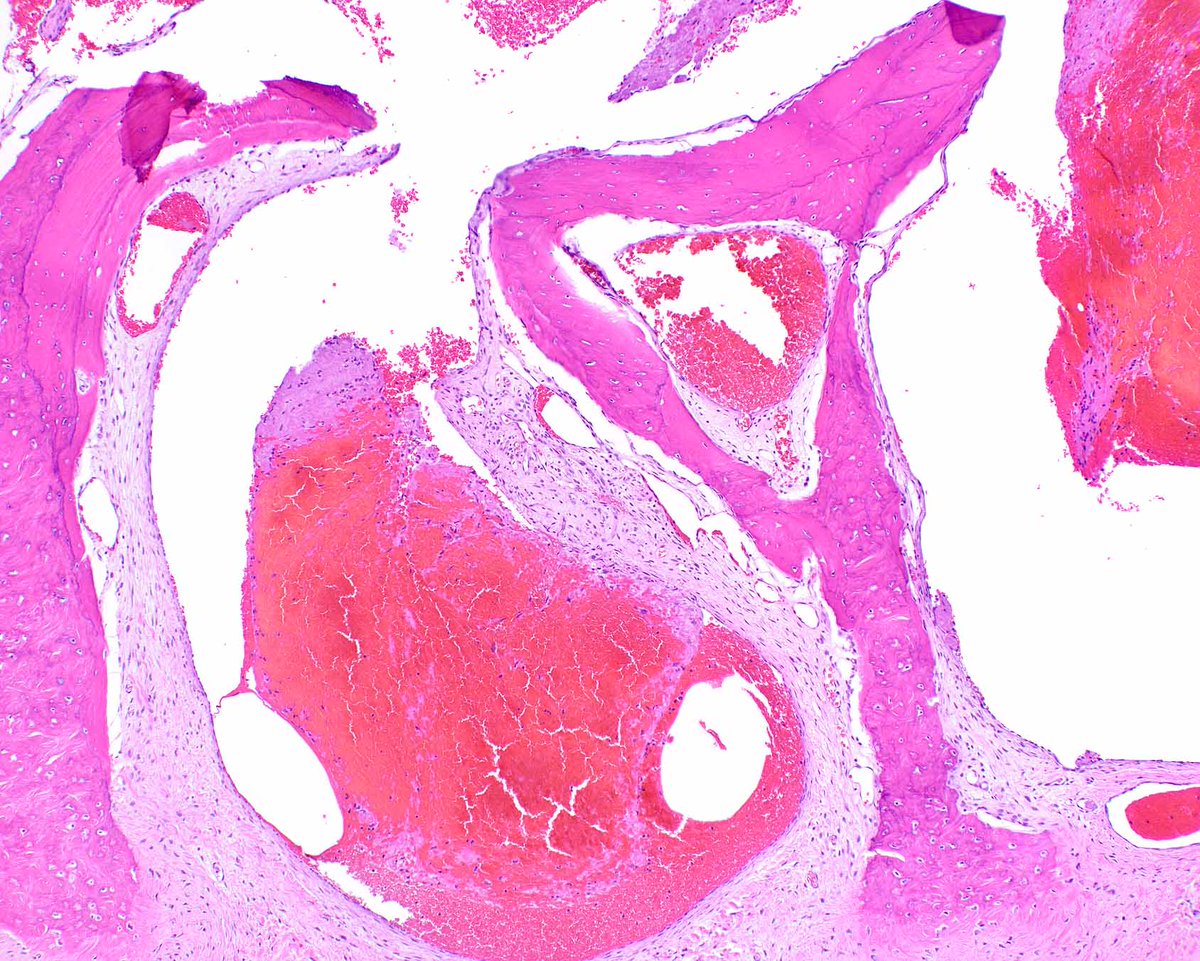

This classic Peutz-Jeghers polyp of the duodenum shows cords of smooth muscle that partition off zones of site specific mucosa. Detecting even a single such polyp can indicate that a patient has this cancer syndrome. PMID: 17667545.

This classic Peutz-Jeghers polyp of the duodenum shows cords of smooth muscle that partition off zones of site specific mucosa.  Detecting even a single such polyp can indicate that a patient has this cancer syndrome.

PMID: 17667545.